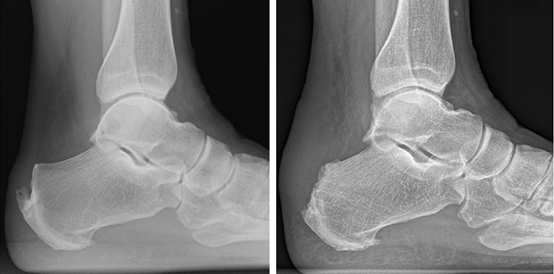

图4:X线检査可见跟腱止点处钙化增生(长箭头), 跟骨后上突增生(箭头)

▶X线检査:可见跟腱止点处钙化、骨化等病变,严重者可见跟骨后上突增生(Haglund畸形)。

图5:CT检査可见跟腱止点处钙化增生(长箭头), 跟骨后上突增生(箭头)